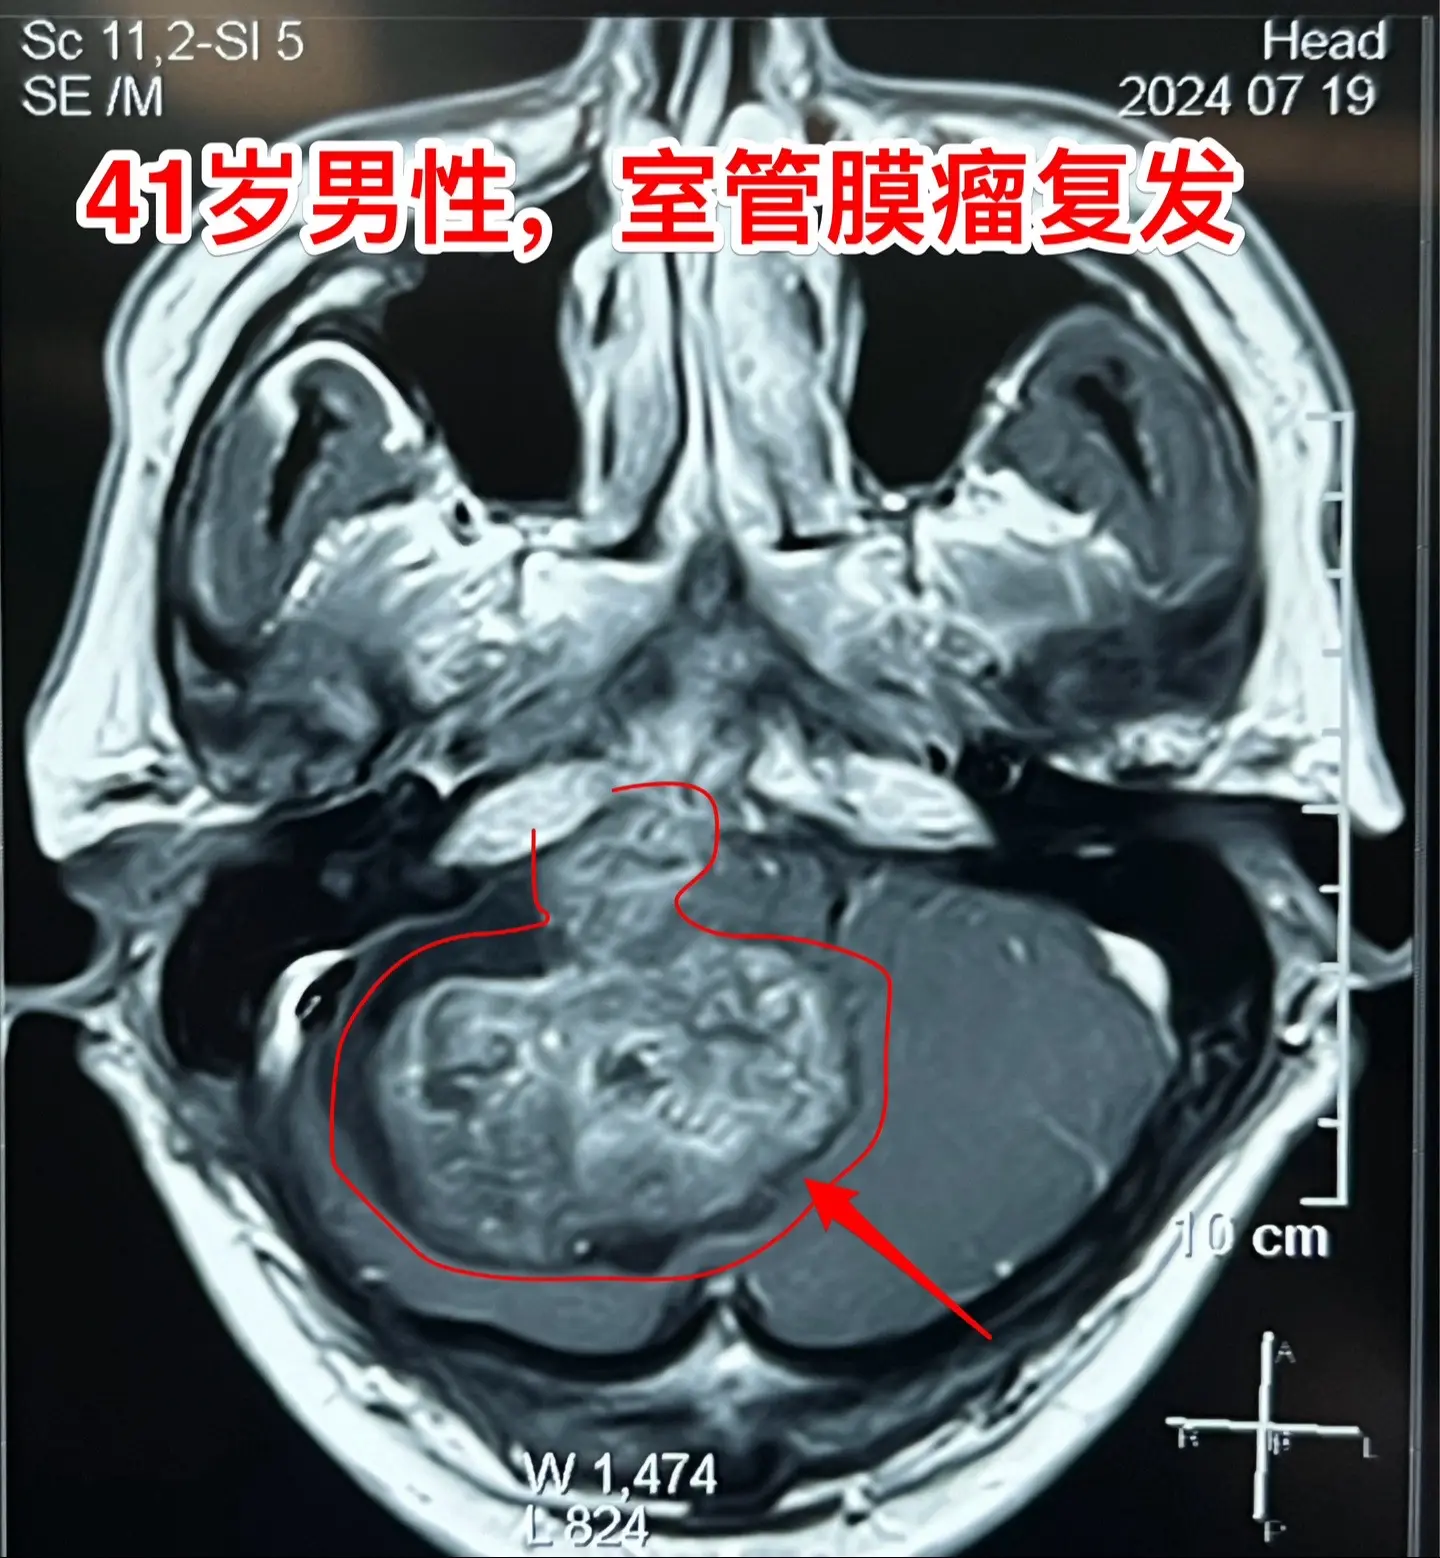

室管膜瘤是良性肿瘤还是恶性肿瘤?41岁的青海省病人,在八年前作过一次开颅手术,现在肿瘤复发了,而且体积很大,脑干实质也受到肿瘤侵蚀,病人有面瘫症状。

室管膜瘤最常见的部位是在小脑,小孩子和大人均可见,即使是完全切除了,想获得治愈是很有难度的,一般认为是恶性肿瘤,化疗、放疗的效果也不确切。

室管膜瘤也可以发生在大脑实质内,一般来说,比小脑的室管膜瘤预后要好。